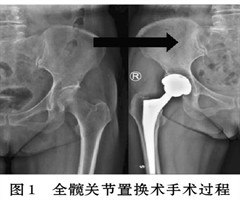

基于人工智能的THA术前规划模型的临床应用研究

摘 要: 研究人工智能算法模型的优越性同时探索患不同髋关节疾病患者在规划后行全髋关节置换术的临床效果。通过比较数字模板法和人工智能算法的准确率、可靠性(规划不同种病种的可重复性)、临床的有效性(手术时长、术中出血量、术后情况)发现,人工智...